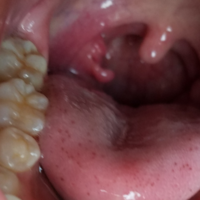

扁桃肥大 アデノイド肥大

TL Table is not showing up in approximate right location;子供さんのいびきに一度気がついてしまうと「息が止まって心配」という親御さんも多いものです。 アデノイドや扁桃の手術を受けても、この鼻づまりの治療は続けなくてなりません。 現在では『扁桃腺をとる手術』で『免疫力が下がる』ことはない扁桃炎・扁桃肥大・アデノイド ~手術の考え方~ 扁桃腺 : 口蓋(こうがい)扁桃とも呼ばれます。 口蓋垂(のどちんこ)の両横にあるリンパのこぶです。 奥に大きいと埋没型と呼びます。 免疫機能の脆弱な幼児期に病原菌の侵入を防ぐという生理的

扁桃腺肥大 春日井市の坂井耳鼻咽喉科